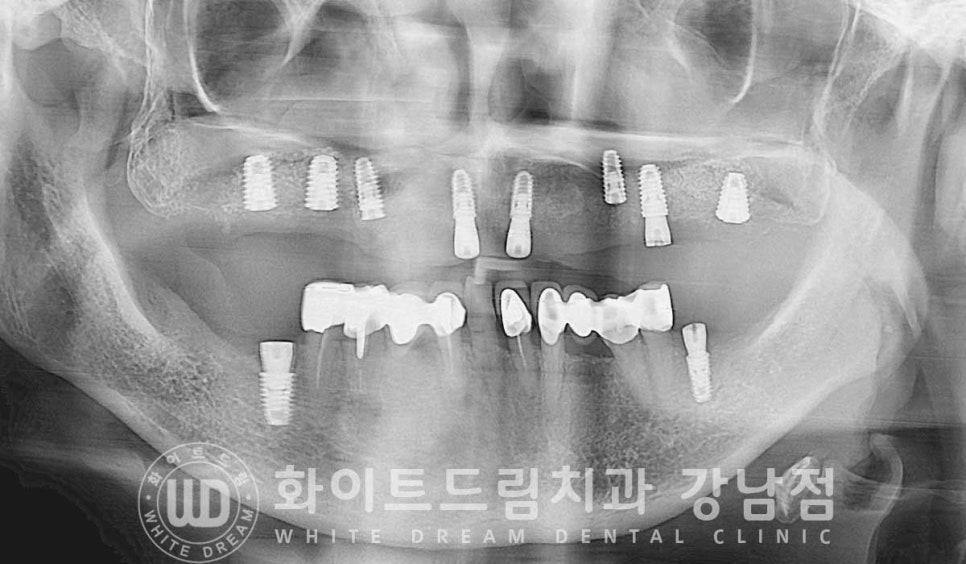

▲ 상악 풀케이스임플란트 수술 후 촬영한 x-ray

수술일자 : 24.02.06

이렇게 한 악에 전체 임플란트를 식립할 때 많은 분들이

몇 개의 임플란트를 심어야 하나요?

하는 문의를 많이 하시는데요.

우리는 한 악당 14개의 치아를 가지고 있습니다. (사랑니 제외)

이 중 식립되는 임플란트의 개수는 치아 개수의 60%를 식립한다고

생각하시면 되는데요.

보통 한 악당 8-9개 정도의 임플란트를 식립한답니다.

환자분도 총 8개의 임플란트를 식립했고, 상악동 거상술도 잘 진행되어

안정적이게 치유 상태를 보이는 상태입니다.